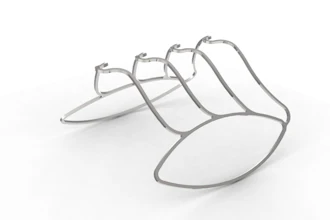

The Injectsense IOP-Connect Sensor Platform sensors in a custom carrier.Injectsense

The Injectsense IOP-Connect Sensor Platform sensors in a custom carrier.Injectsense